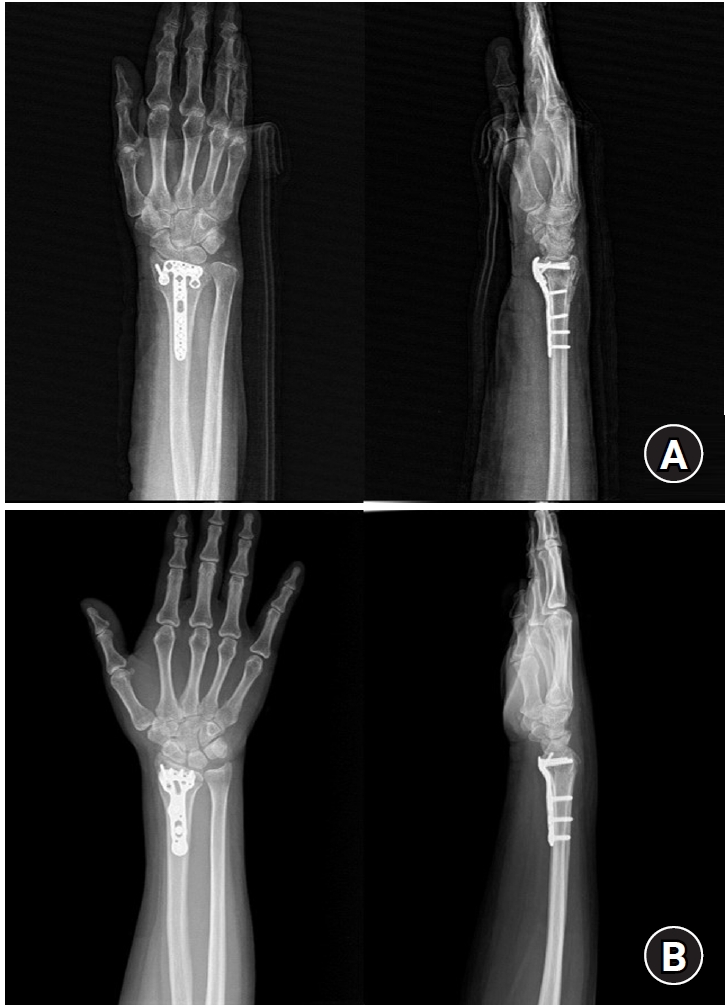

Fig. 3.

Postoperative radiographs (anteroposterior and lateral). (A) Volar articular marginal fragment of the distal radius fixed by two plates: a standard 2.4 mm LCP-L distal radius plate (Synthes) and a 2.0 mm locking compression plate distal ulnar hook plate (Synthes). (B) Additional percutaneous pinning after plating. (C) Additional percutaneous pinning and external fixator after plating.

jmt-2025-00241f3.jpg

Fig. 4.

Postoperative radiographs (anteroposterior and lateral). (A) A 2.4 mm variable angle locking compression plate volar rim distal radius plate (Synthes) used for fixation in a distal radius fracture with a volar lunate facet fragment. (B) Acu-Loc volar distal radius plate (Acumed) used for fixation in a distal radius fracture with a volar lunate facet fragment.

jmt-2025-00241f4.jpg